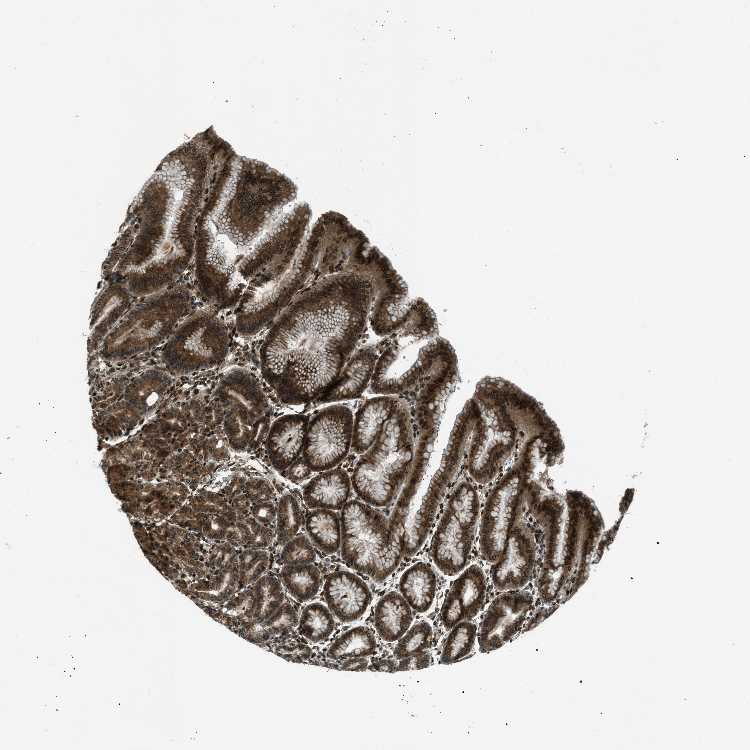

TISSUE PRIMARY DATA STOMACH Show tissue menu

STOMACH 1 - Antibody stainingi

Antibody staining in the annotated cell types in the current human tissue is reported as not detected, low, medium, or high, based on conventional immunohistochemistry profiling in selected tissues. This score is based on the combination of the staining intensity and fraction of stained cells.

Each image is clickable and will lead to virtual microscopy that enables deeper exploration of all samples and also displays staining intensity scores, fraction scores and subcellular localization as well as patient and tissue information for each sample.

Antibody HPA017340

Glandular cells Medium

STOMACH 2 - Antibody stainingi

Glandular cells High